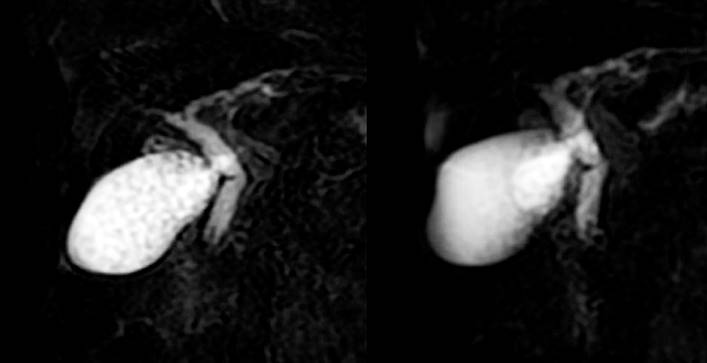

Paciente de 84 años con antecedente de gastrectomía radical total y reconstrucción en Y-de-Roux por adenocarcinoma gástrico moderadamente diferenciado en 2012. Consulta por dolor tipo cólico en el hipocondrio derecho de 9 horas de evolución, náuseas, ictericia y coluria. En el examen físico se encontró una paciente ictérica, con signos vitales normales, abdomen doloroso a la palpación en el hipocondrio derecho y signo de Murphy negativo. En los paraclínicos se encuentra un perfil colestásico (Tabla 1), una ecografía hepatobiliar con colelitiasis y vía biliar normal, una colangiorresonancia con colelitiasis múltiple, signos de colecistitis aguda en la fase inicial y dilatación de la vía biliar extrahepática (colédoco de 11 milímetros), con microcálculos en su porción distal (Figura 1). Después de discutir el caso entre los servicios de cirugía general y gastroenterología, se decide llevar a una colecistectomía laparoscópica con enteroscopia intraoperatoria para el manejo de la coledocolitiasis.

Figura 1 Colangiorresonancia que demuestra colelitiasis múltiple, dilatación de la vía biliar extrahepática y coledocolitiasis. Fuente: archivo de los autores.